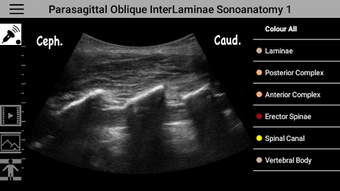

AnSo Anesthesia Sonoanatomyé um programa gratuito para Android, que pertence à categoria 'Medical' .

AnSo Anesthesia Sonoanatomy está disponível para Android 9.0 ou superior. A versão atual do programa é 2.1.47, e você pode executá-lo apenas em inglês.